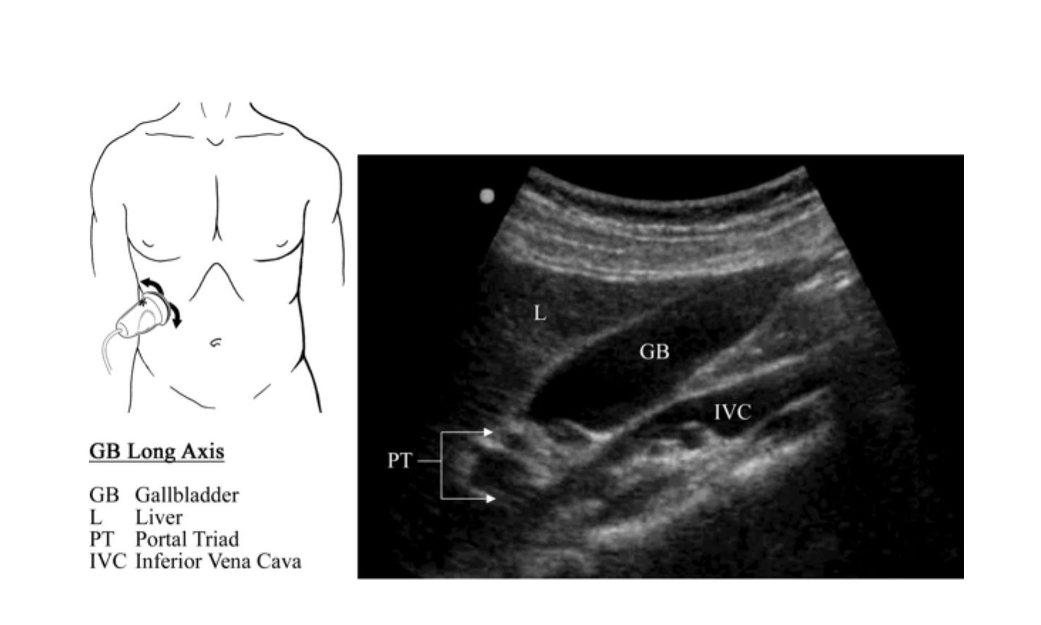

Evaluating for Gallbladder and Biliary Disease

For patients presenting with right upper quadrant (RUQ) or epigastric abdominal pain suggestive of gallbladder or biliary disease, ultrasound can be used to further evaluate the patient. RUQ or epigastric abdominal pain associated with nausea, vomiting, fever, jaundice and/or lab abnormalities (AST, ALT, ALK phos, Bili, Lipase, WBCs with epigastric pain) further increases suspicion for disease.

Normal Anatomy on Ultrasound

REVIEW: pages 54-65Biliary RUQ POCUS Exam